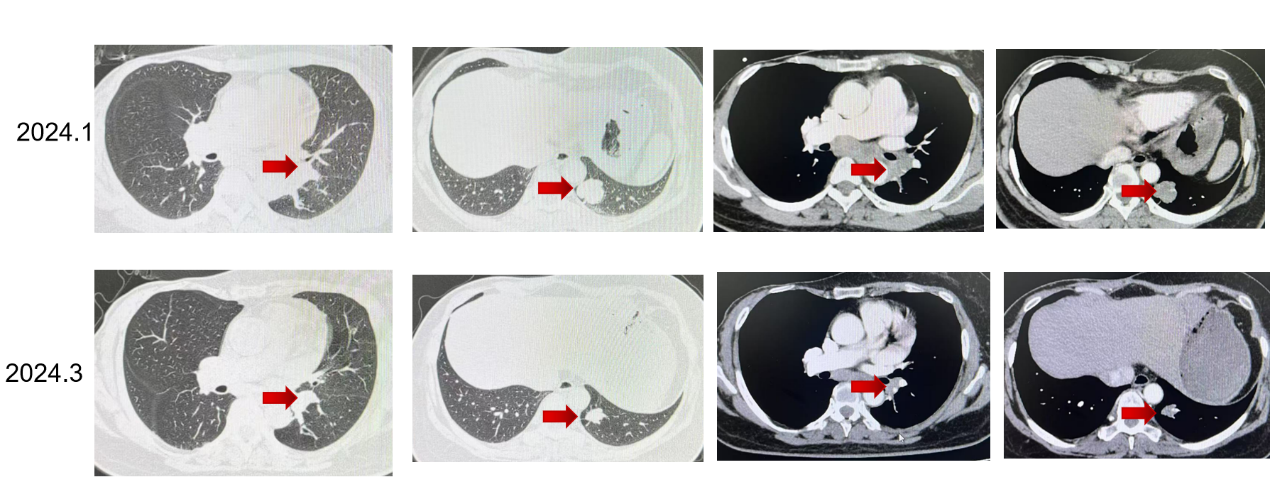

初始疗效评价:2024年3月复查较2024年1月基线相比,病灶较前缩小,疗效评价为SD(伴肿瘤缩小)。

更换治疗方案:2024年6月,患者改用达尔西利150 mg,口服3周停1周,联合阿那曲唑1 mg qd治疗。

换用达尔西利联合阿那曲唑后,患者后续多次复查均提示病灶进一步缩小,2024年8月、2024年11月、2025年4月及2025年9月疗效评价均为PR。靶病灶总和由55 mm降至20 mm,整体缩小约63.6%,提示调整方案后患者获得了持续且稳定的影像学缓解。